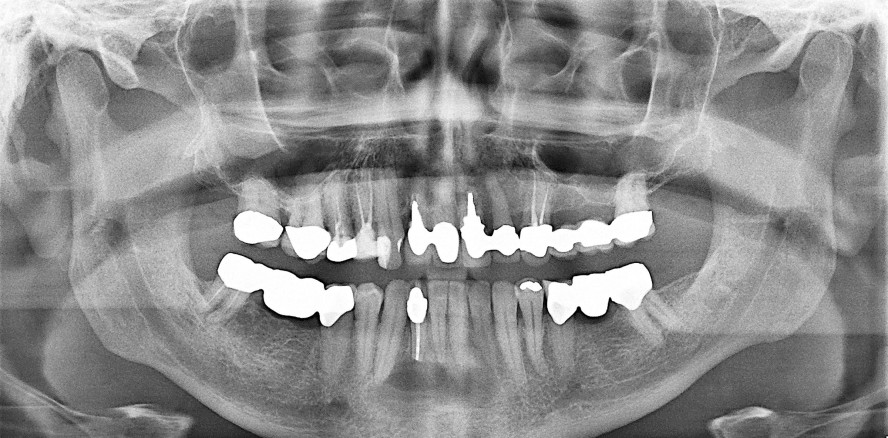

Ein 53-jähriger männlicher Patient stellte sich mit leichten Beschwerden im Bereich des Zahns 42 bei seinem Hauszahnarzt vor. Der Zahn war vor einiger Zeit mit einer Krone prothetisch versorgt worden. Es erfolgte eine klinische und radiologische Kontrolle des Befundes. Der Zahn 42 reagierte nicht auf einen Kälteimpuls und wurde deswegen in der zahnärztlichen Praxis wurzelgefüllt und primär reseziert. Abbildung 1 zeigt den radiologisch unauffälligen Befund eines OPGs vor der Resektion des Zahns 42.